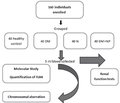

Авторы:

Doaa Hazem Mohammed (1, 2), Meethaq Sattar Abood (2), Ali Naeem Salman (2)

(1) - Department of Pharmaceutical Sciences, College of Pharmacy, University of Thi-Qar, Thi-Qar, Iraq

(2) - Department of Biology, College of Education for Pure Science, University of Thi-Qar, Thi-Qar, Iraq

Журнал «Почки» Том 14, №4, 2025